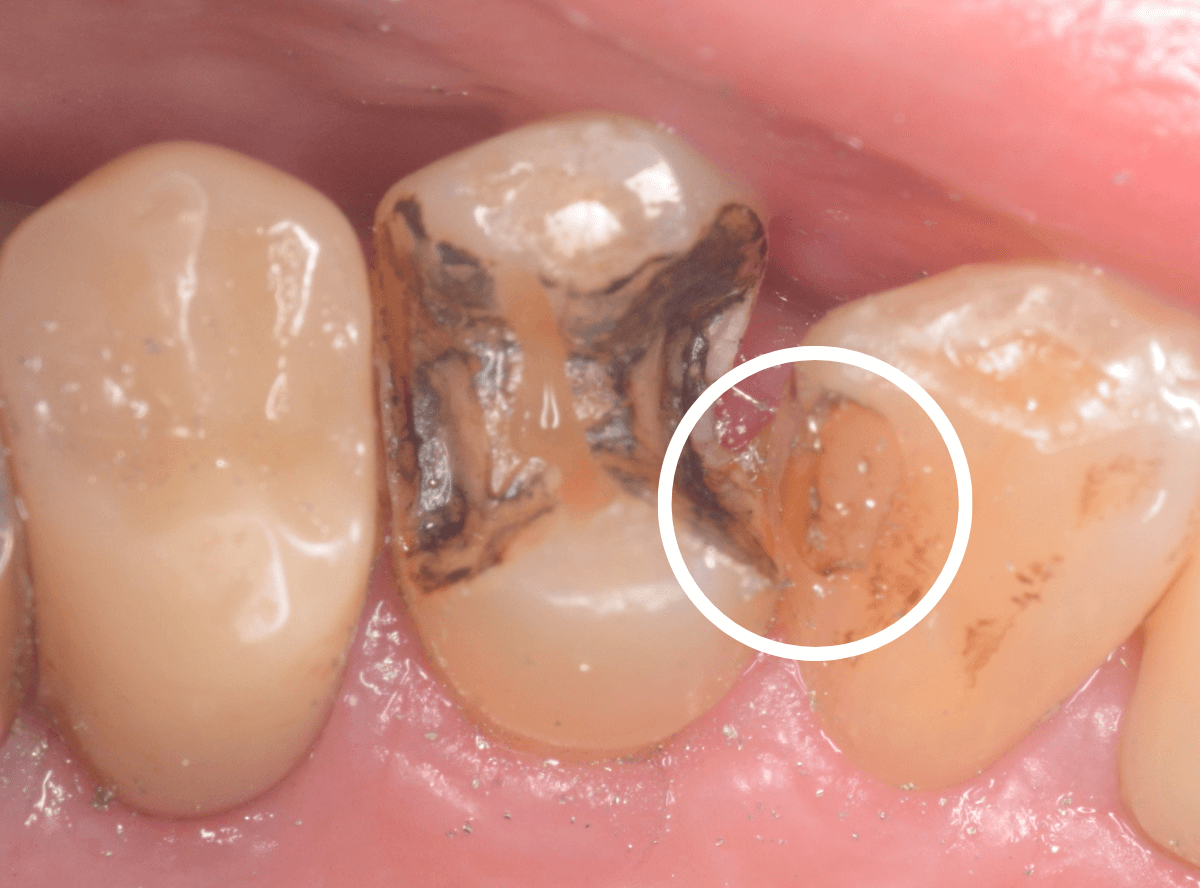

今回は、上の奥歯の銀歯(メタル・クラウン)の中で虫歯になってしまった方です。

通常は、さし歯の中が虫歯になってしまうと、レントゲンにも写らず見つけづらいのですが・・・。

歯を裏側から見たところです。

幸い、見える部分に虫歯が

さし歯と歯肉の間に虫歯ができているのがわかります。

歯の奥まで虫歯が進んでいるのか、浅い虫歯ですんでいるのかは治療をしながら調べていく必要があります。